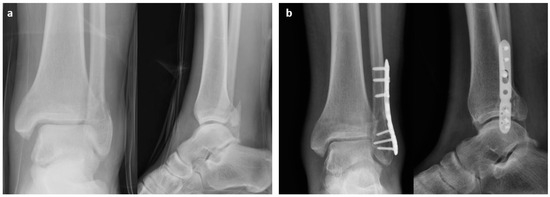

2.1. Surgical Procedure

3. Results